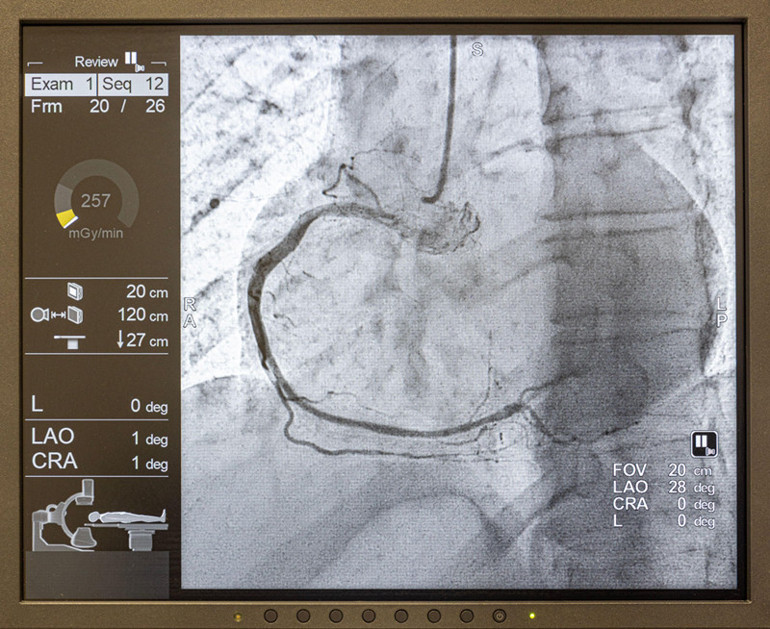

Bilgisayarlı tomografi (BT) / Anjiyografi:

Kullanılan kontrast maddeler iyot (iodine) içerir. Bu maddeler X-ışınlarını güçlü şekilde soğurur.Böylece kontrast verilen bölgeler görüntüde daha parlak görünür.